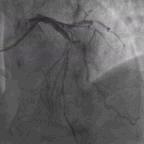

接下来的问题是结束手术,还是锦上添花处理回旋支或继续处理前降支中段?因前降支中段涉及很大的对角支,如果在前降支中段植入支架势必会影响对角支血流,既然前降支血流明显改善,冒此风险不值得,故未在前降支中段植入支架。最终我们决定一不做二不休处理回旋支,考虑回旋支OM2最大,但有慢性闭塞病变,处理起来不容易,遂决定处理回旋支远端,将Rinato导丝送至回旋支远段,用小球囊Ryujin(1.5*8)扩张(图7)后血流改善(图8),最终结束手术。

图7. 小球囊Ryujin(1.5*8)扩张

图8. 最终结果